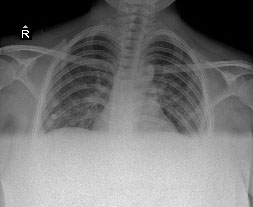

The 21-year-old woman was admitted to the department of obstetrics and gynecology at the gestational age of 37 weeks with bleeding. There was no feature in her medical history. She was a housewife, gravida 1, parity 0. Her pregnancy was terminated by cesarean section due to placenta ablation and intrauterine ex-fetus. Erythrocyte suspension was transfused for intraoperative bleeding and low postoperative hemoglobin value. An anaphylactic reaction developed in the patient during blood transfusion (after about 100 ml). Deep hypotension, bilateral diffuse bronchospasm and anasarca edema were observed to the patient. Adrenaline (1:10000) was administered intravenously to the patient andinvasive blood pressure monitoring was performed. She was taken to the intensive care unit. The Glaskow coma score (GCS) was 14, physical examination was normal and she had not hypotension and tachycardia. Laboratory findings were hemoglobin: 7,4 g/dl, hematocrit: 23%, platelet: 75000, creatinine: 1,19 mg/dl, lactate dehydrogenase (LDH): 508 U/L, calcium: 6,6 mg/dl.  The Following hemoglobin was 5,5 g/dl thus 3 units of washed erythrocyte suspension were transfused to the patient. The patient complained of dyspnea, orthopnea, and lower limb edema after 3 hours from the blood transfusion. Oxygen saturation was 84% in room air. On auscultation, bilateral inspiratory rales were heard at all zones of the lungs and she had bilateral marked pretibial edema. Four liters/minute of nasal oxygen, diuretic (furosemide intravenous) and anticoagulant (enoxaparin 6000 unit 2x1 subcutaneously) were given with predicted pulmonary edema and pulmonary thromboembolism. D-dimer (2.56 μg/ml), troponin-T (123 pg/ml) and LDH (505 U/L) were high. Her arterial blood gas analysis showed pH: 7,52; pO2: 69,6 mmHg; pCO2: 36,2 mmHg; HCO3: 29,2 mmol/L; SO2: 86%. Bilateral infiltrations especially at the middle and lower zones and cardiomegaly were notable on the chest x-ray (Figure 1). The bedside transthoracic echocardiography showed normal right ventricles, pulmonary artery pressure of 30 mmHg, left ventricular EF of 40% by Teicholz and Simpson’s methods (Figure 2). The case was diagnosed with PPCM and she was given treatment consisting of an angiotensin-converting enzyme inhibitor and furosemide. Regression was observed on control chest X-ray (Figure 3). Control levels of D-dimer (2,21 μg/ml), troponin-T (81 pg/ml) and LDH (450 U/L) decreased. When the clinical state findings improved, she was transferred to Department of Obstetrics and Gynecology. The patient was discharged after 5 days.

Figure 1 The chest x-ray. A chest x-ray shows bilateral infiltrations at the middle and lower zones, and cardiomegaly consistent with pulmonary edema.